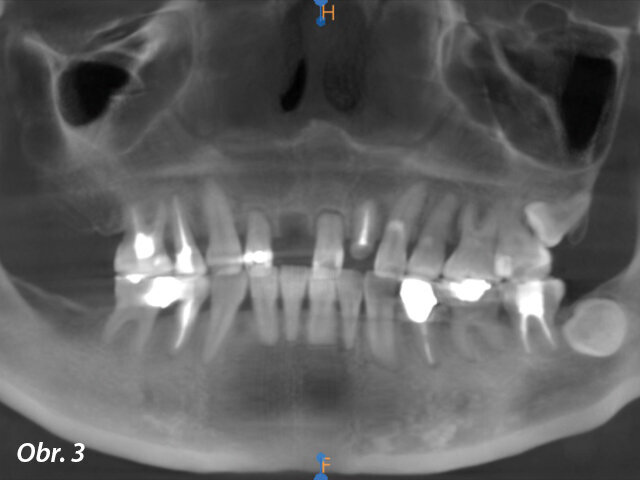

Na naše pracoviště se dostavila čtyřicetiletá pacientka, která před třemi týdny následkem synkopy utrpěla úraz horních frontálních zubů. Při klinickém vyšetření jsme diagnostikovali avulzi zubu 11 a korunky zubů 12 a 21 byly ulomené 3–5 mm pod úrovní gingivy s mobilitou III. stupně. Dále jsme zjistili zlomeninu korunky zubu 22 s lomnou linií končící ekvigingiválně. Ostatní zuby nevykazovaly žádné zjevné patologie či abnormality (obr. 1–4). Po vyloučení celkových onemocnění jsme se rozhodli pro ošetření pomocí implantátů s důrazem na estetiku a funkci.